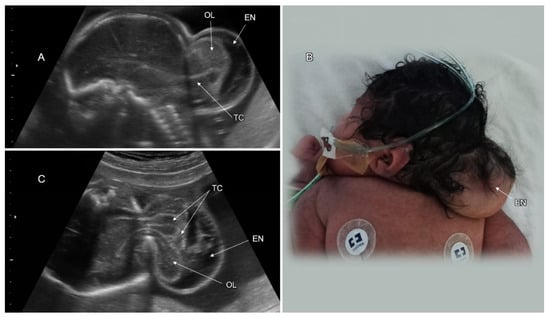

3.1. Cranial NTD

3.2. Spinal Dysraphism